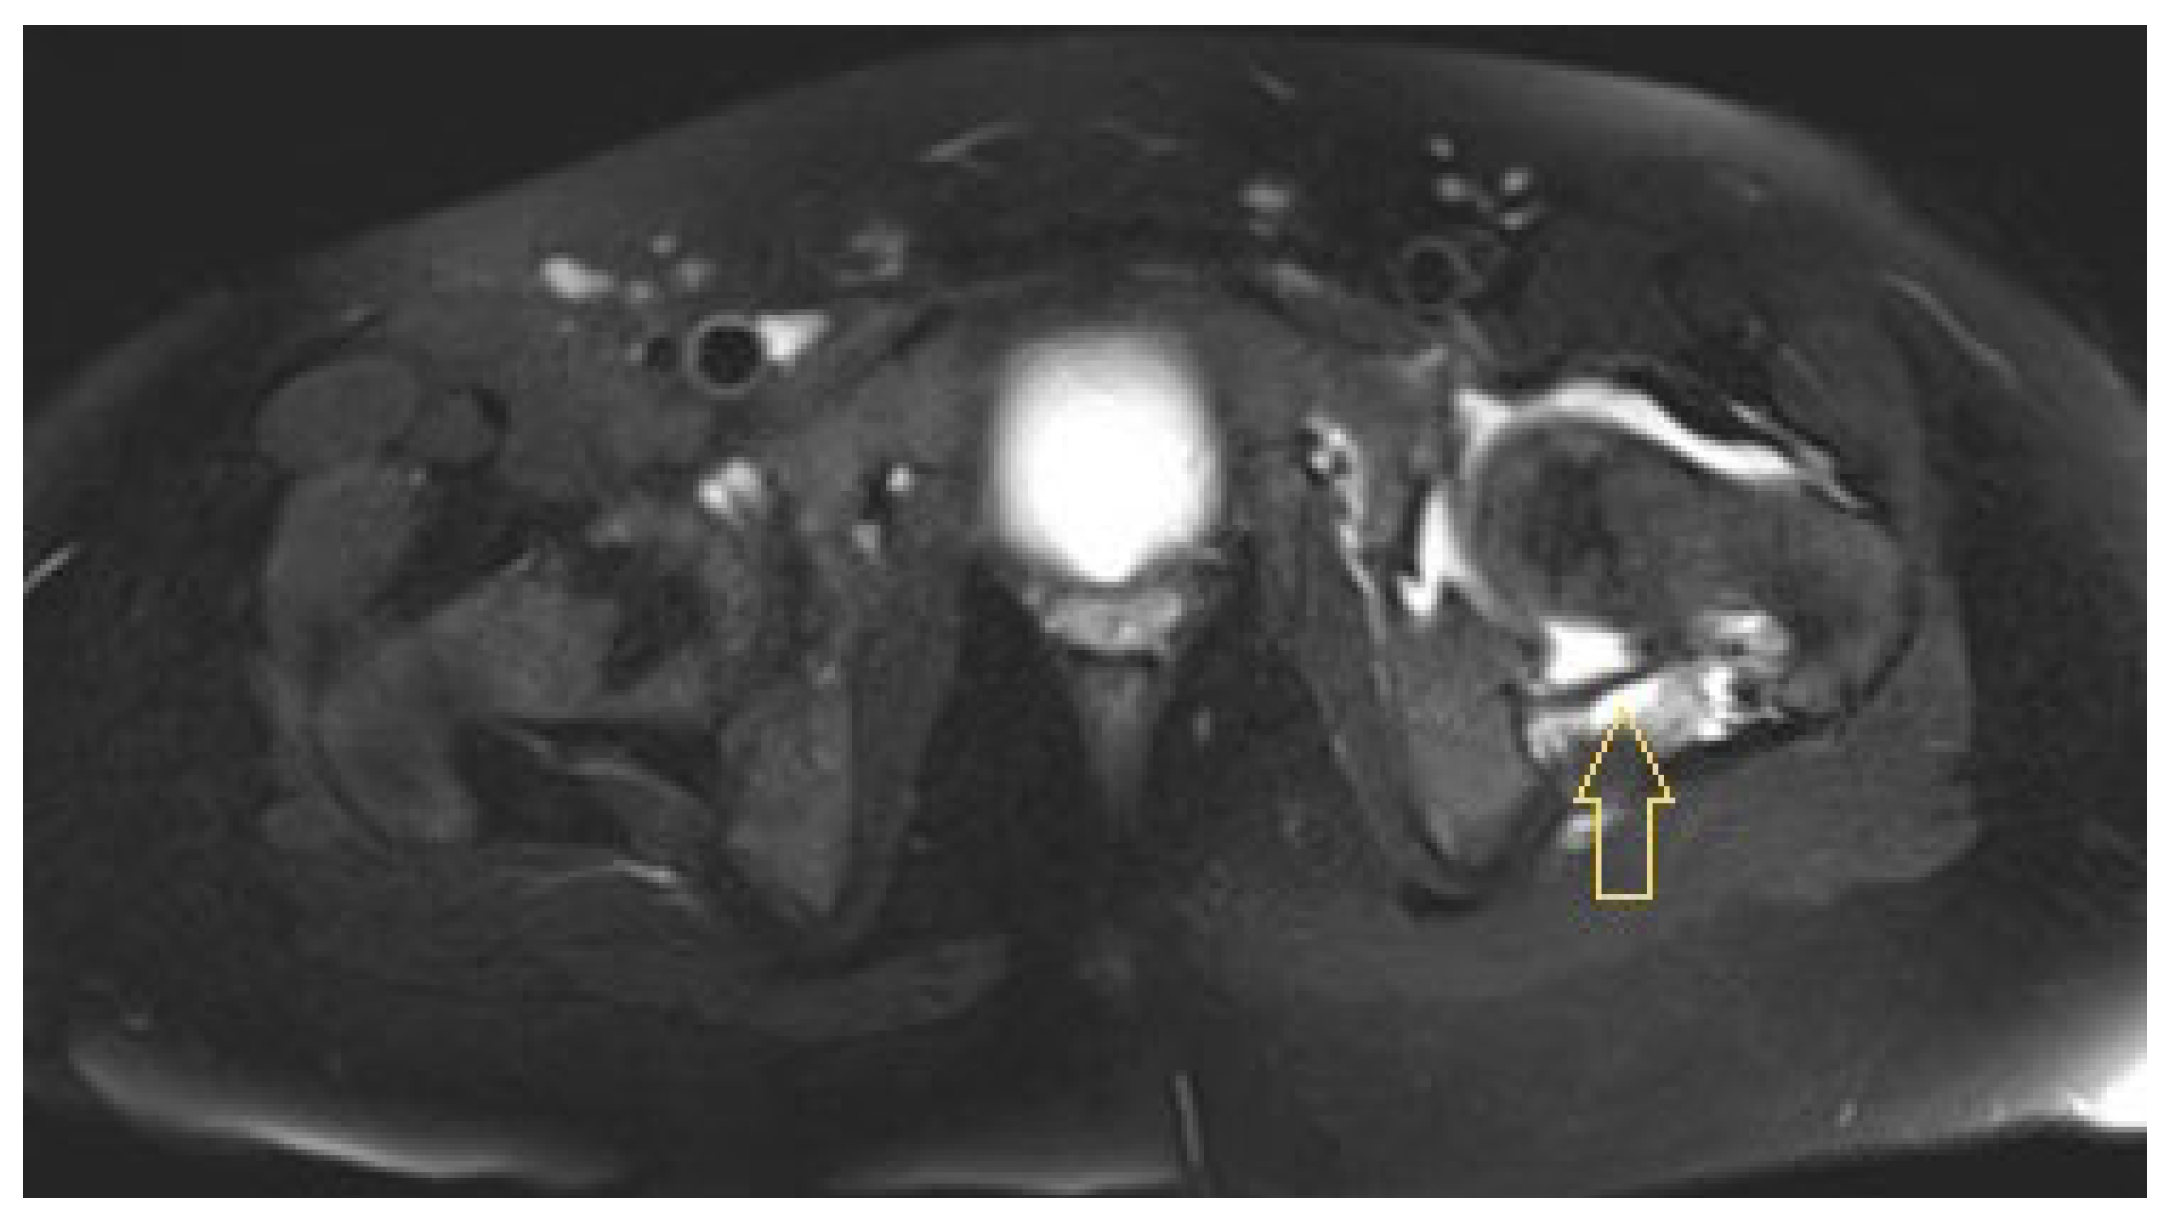

3.1.1. Patient 1

3.1.2. Patient 2

3.1.3. Patient 3